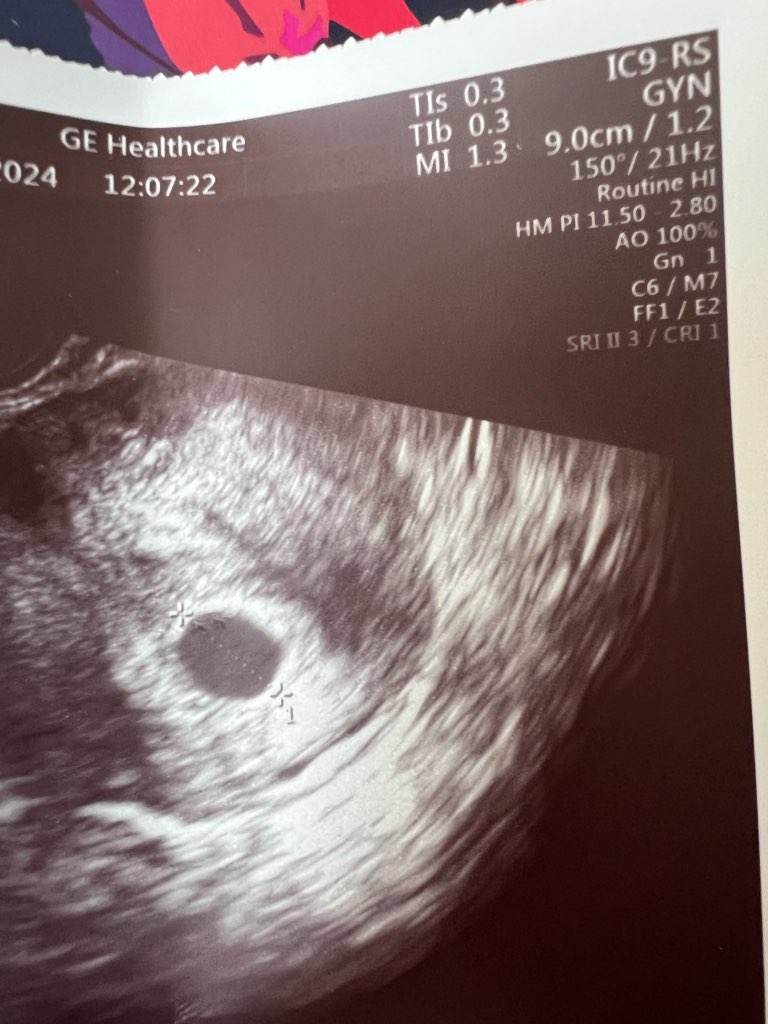

na każdym przeważnie jestA na usg nie macie napisanych wymiarów YS i GS? Ja to dopiero po czasie odkryłam, bo mój lekarz też małomówny.![]()

a jednak zmierzył nawet nie dopatrzałam. 9 cmnie. Właśnie nie zmierzył

1,65 cm na dole mam opisa jednak zmierzył nawet nie dopatrzałam. 9 cm